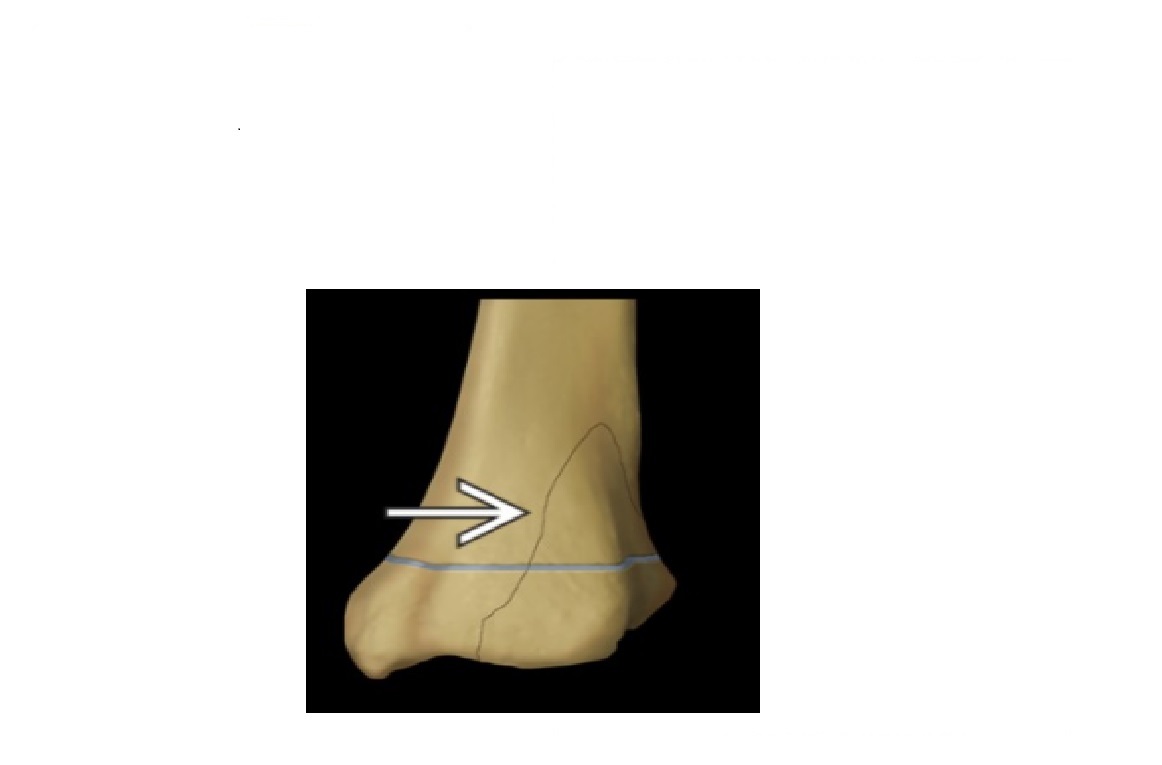

Tillaux fracture

Salter-Harris 3 = through the anterolateral distal tibial epiphysis

Triplane fracture

Salter-harris 4 =Vertical component through the epiphysis , horizontal component through the physis , oblique through metaphysis